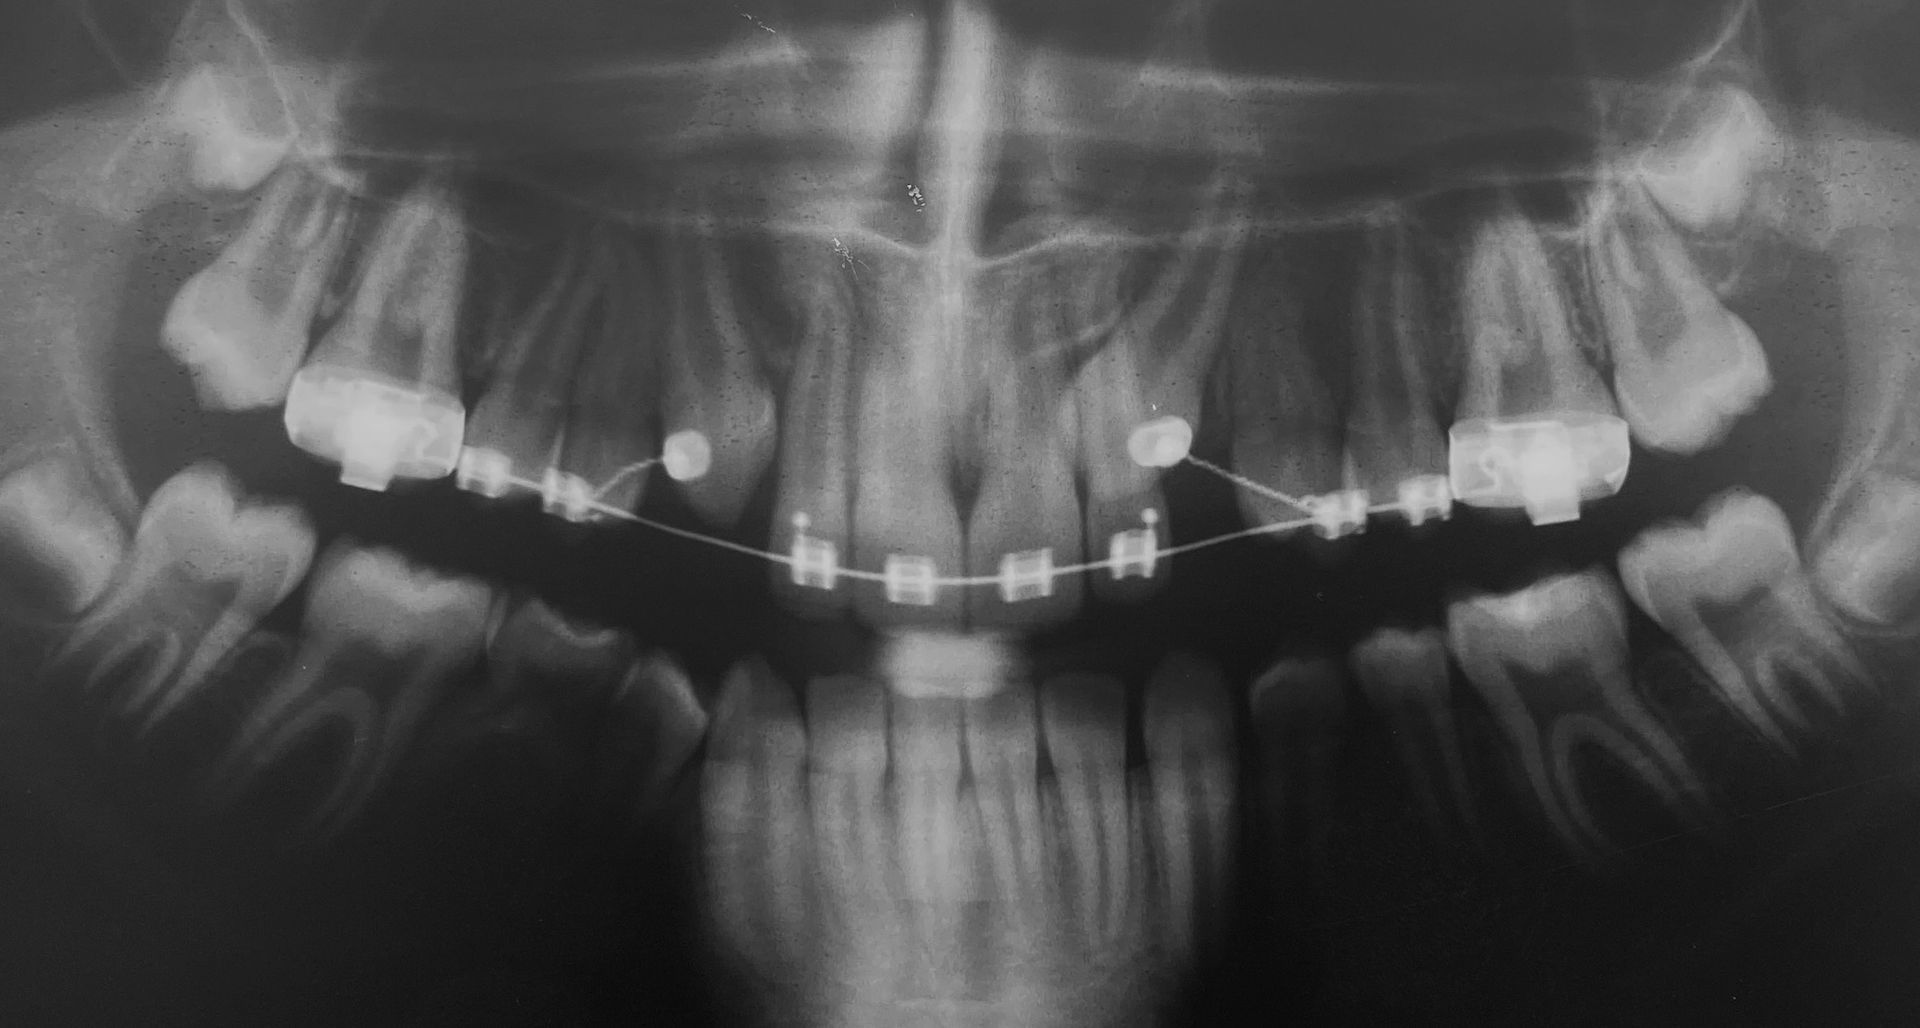

Agganciamento dei canini superiori inclusi

Canini superiori inclusi

Agganciamento canini superiori inclusi

Entrambi i canini sono stati agganciati chirurgicamente per l'allineamento